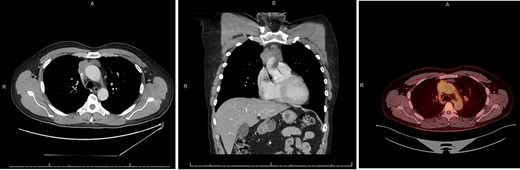

A 55-year-old male initially presented to his primary care provider with diplopia and eyelid droop. He was diagnosed with MG via confirmation of positive acetylcholine receptor blocking antibodies. CT chest revealed a complex, multilobulated, 6 cm anterior mediastinal mass compressing the SVC and possibly involving the central aspect of the left innominate vein(Fig. 1). A core needle biopsy was obtained, and pathology was consistent with type B2 thymoma, with no evidence of carcinoma. A positron emission tomography (PET) scan was also obtained, which revealed a maximum standard uptake value (SUVmax) of 3.0. Treatment was discussed across multiple disciplines at multiple institutions, with differing opinions regarding neoadjuvant chemotherapy, definitive chemoradiation due to unresectability, versus upfront surgical resection. Our facility, a major regional thoracic oncology center, was consulted and recommended upfront surgical resection followed by likely adjuvant radiation.

CT chest axial (left), coronal (middle) and PET (right) of invasive thymoma.

It is important to differentiate between invasive thymoma and thymic carcinoma, as the disease free and long-term survival are significantly different, and thus when feasible, biopsy is recommended [4]. In cases of thymic carcinoma, definitive chemoradiation is often the treatment of choice, given the much poorer prognosis [3]. In addition to CT, PET has also been described for determining invasiveness and prognosis. Tumors with a high SUVmax have an increased likelihood of carcinoma, with some studies reporting a value of 6 to predict carcinoma with high sensitivity [6]. Thymomas with higher SUVs have been thought to be associated with more invasive disease, although this has been shown to be much less predictable [6], as in this case, where the tumor had low SUV uptake despite having a high degree of invasion upon intraoperative assessment.